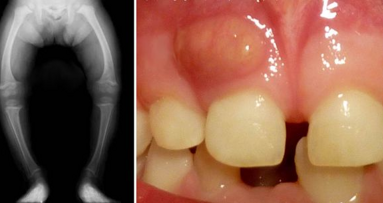

Bien que ce protocole soit recommandé pour tous les traitements endodontiques (Figs. 10, 11, 12 et 13), il est plus précieux dans les situations cliniques suivantes :

_Cas infectés avec radiotransparence apicale, latérale et / ou furcale.

_Retraitements avec parodontite périapicale.

_Cas d’inflammation aigue, surtout ceux diagnostiqués avec le syndrome de dent fêlée.

_Résorption interne et externe.

_Infections persistantes ne répondant pas au traitement endodontique conventionnel.

_Inconfort postopératoire prolongé, inexpliqué.